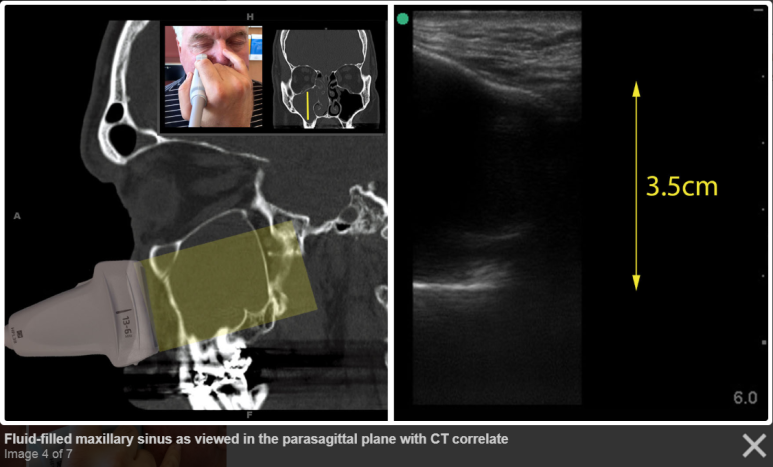

물이 찬 부비동의 CT / US image